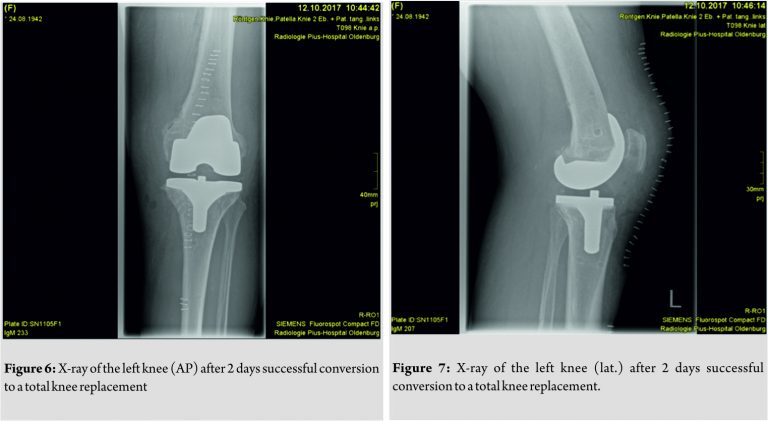

In November 2017, the patient underwent conversion of the KineSpring system to a total knee replacement (Vega Femur Size 5 narrow, Columbus Tibia Size 2, PE-Inlay PS 12 mm, Aesculap, Germany). The procedure was performed without any difficulties. Removement of the KineSpring system added an additional 11 min to the operation time. Implementation of the Columbus total knee replacement (Aesculap, Germany) followed our standard techniques and was not complicated by the former KineSpring system. Post-operative radiographs showed that the femoral and tibial implants were placed properly (Fig. 6 and 7). Post-operative course was good, and the patient was discharged 10 days postoperatively to rehabilitation. 3months after surgery, she is pain free, mobilizing without any walking aid and with a more than satisfactory range of motion of her left knee.